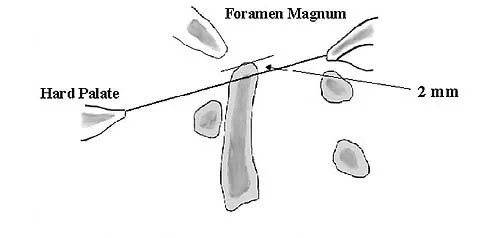

The illustration shown in Figure 19 shows a Chamberlain line. What is the most likely diagnosis?

Explanation